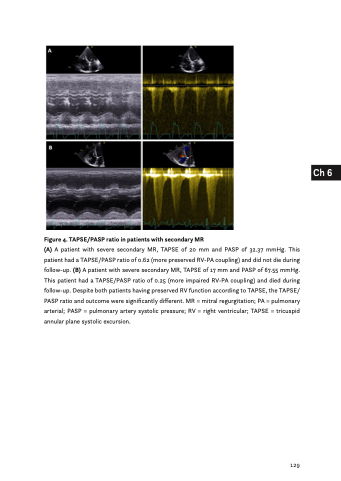

Figure 4. TAPSE/PASP ratio in patients with secondary MR

(A) A patient with severe secondary MR, TAPSE of 20 mm and PASP of 32.37 mmHg. This patient had a TAPSE/PASP ratio of 0.62 (more preserved RV-PA coupling) and did not die during follow-up. (B) A patient with severe secondary MR, TAPSE of 17 mm and PASP of 67.55 mmHg. This patient had a TAPSE/PASP ratio of 0.25 (more impaired RV-PA coupling) and died during follow-up. Despite both patients having preserved RV function according to TAPSE, the TAPSE/ PASP ratio and outcome were significantly different. MR = mitral regurgitation; PA = pulmonary arterial; PASP = pulmonary artery systolic pressure; RV = right ventricular; TAPSE = tricuspid annular plane systolic excursion.